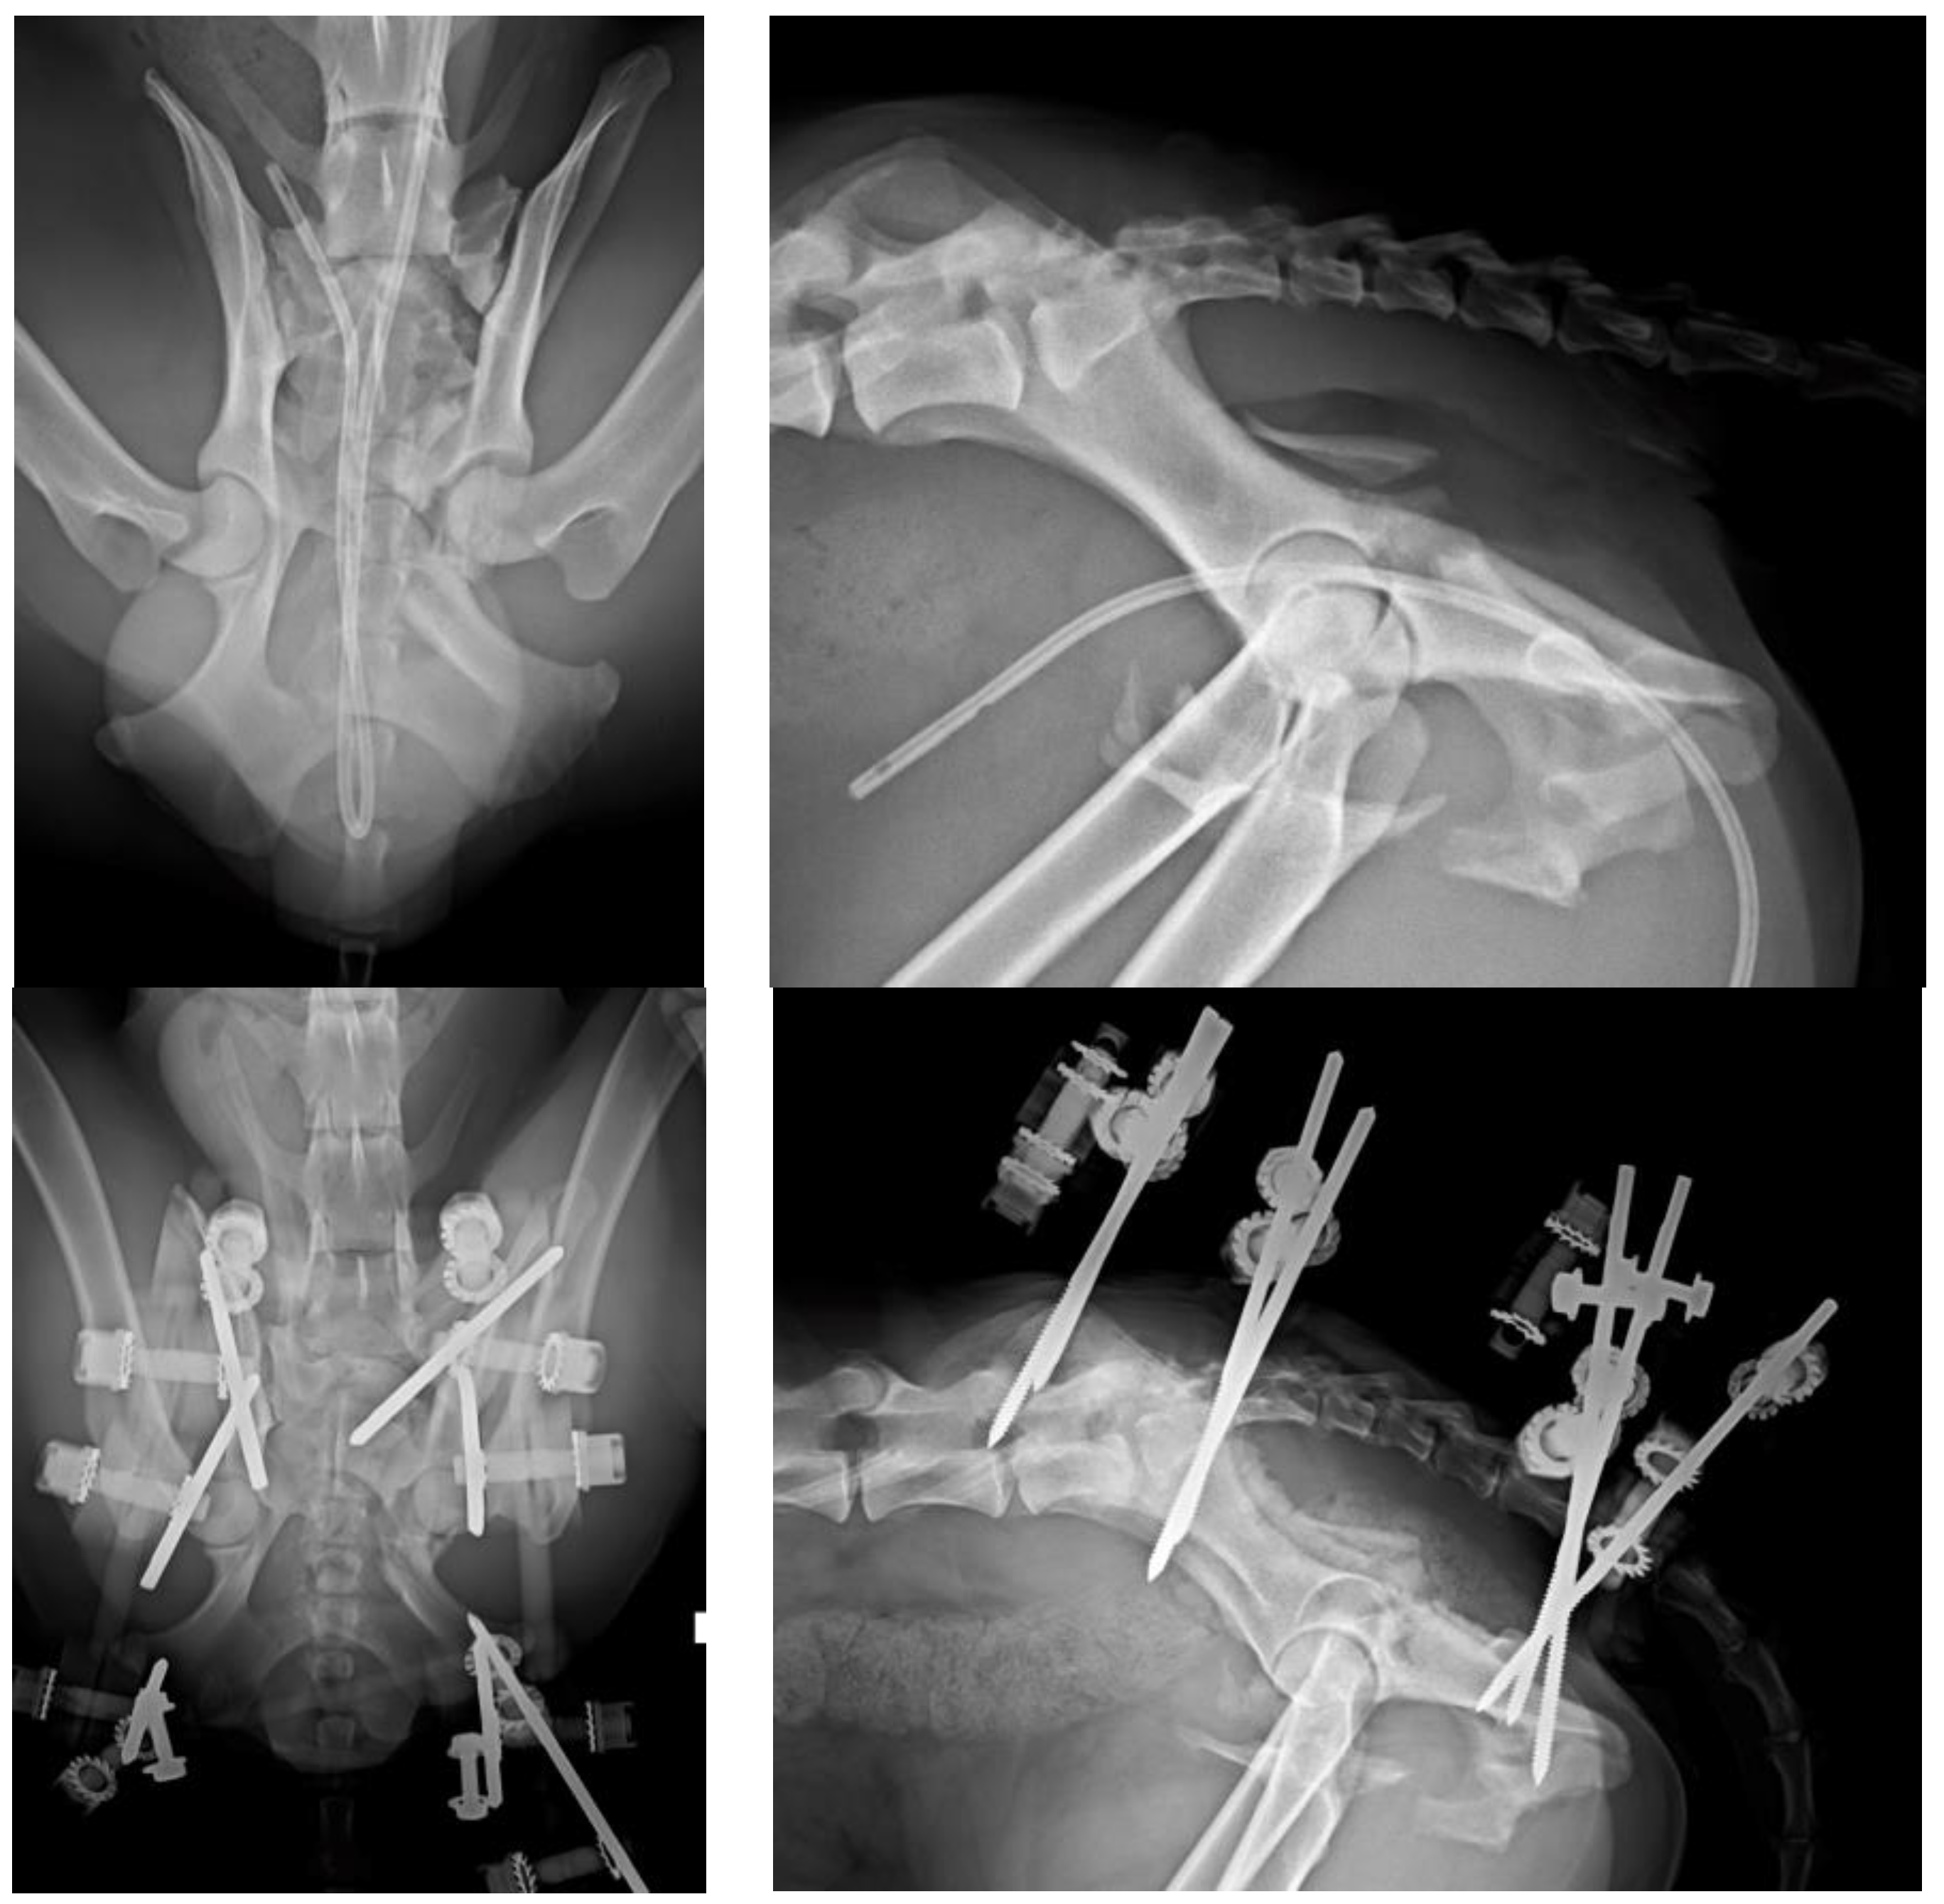

Figure 6. (Top left): VD projection of a patient with left acetabulum, ischial and pubic fractures. Note the fracture of the left articular process of the sacrum. (Top right): Lateral projection of the same patient. (Bottom left): The fractures were stabilized by a type O radiolucent EF. The radiolucent components of the EF provide a better visualization of the bone. (Bottom right): PO lateral projection of the patient.